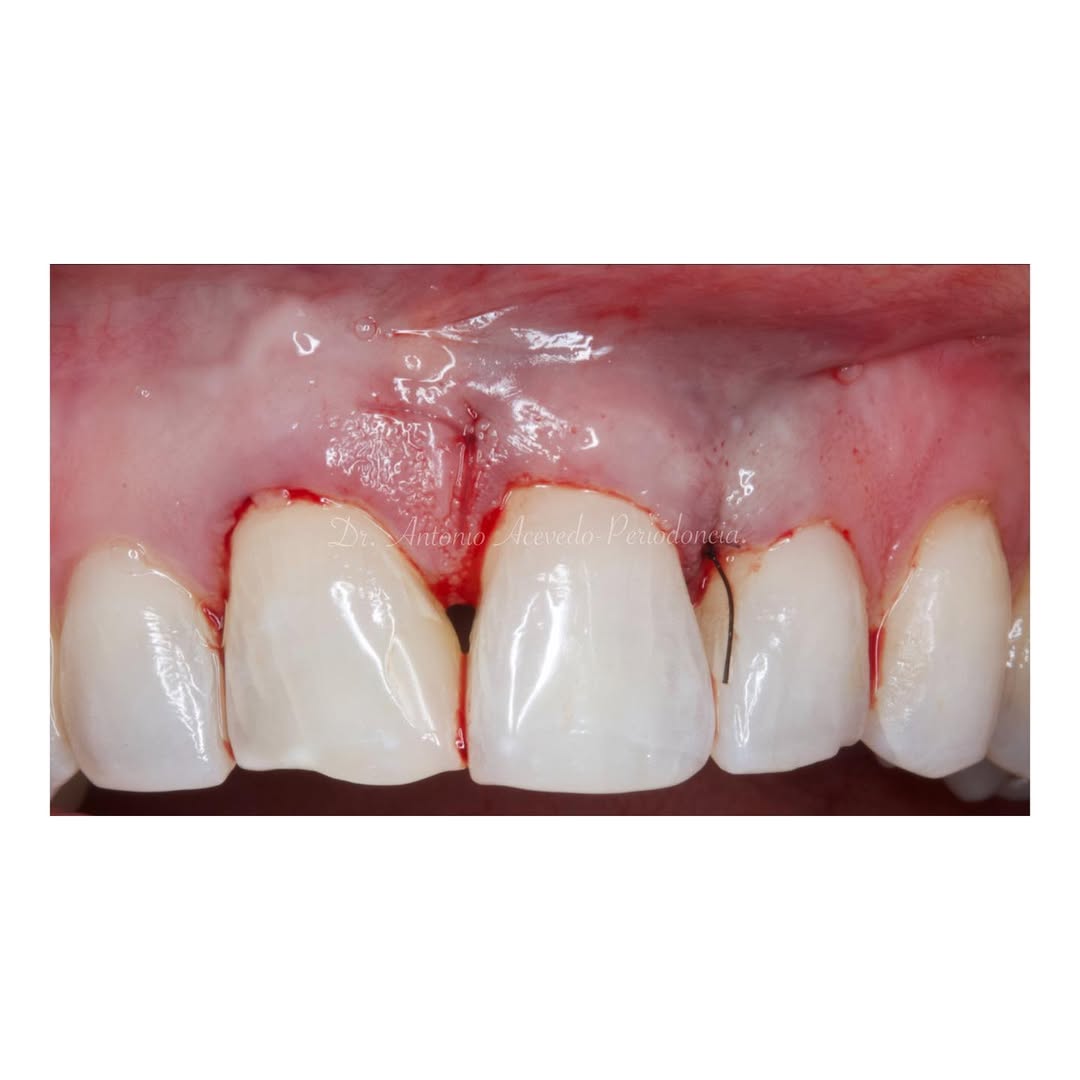

Se realizará todo el procedimiento con un microscopio operatorio, lo que permite al alumno ver toda la cirugía en directo en una pantalla en la sala de cirugía.

La formación comenzará con la presentación del caso clínico que se abordará durante el curso, seguida de una cirugía en directo, que permitirá observar paso a paso el procedimiento y la toma de decisiones clínicas. Durante la jornada se profundizará en los conceptos biológicos aplicados a

Durante una mañana, asistirás a una Cirugía Mucogingival de recubrimiento radicular de una recesión unitaria en 31 con frenillo asociado. Gracias al uso del microscopio y a la proyección en tiempo real en pantalla, verás exactamente lo mismo que veo yo durante la cirugía, sin tener que estar

Toda la cirugía se llevará a cabo con un microscopio operatorio y el paciente estará bajo sedación consciente.

Ya se han realizado la extracción de los dientes 12, 11, 21, 22 para garantizar el cierre de tejidos blandos. El día de la cirugía, el alumno verá todo el procedimiento en una pantalla en directo en la sala de cirugía, ya que todo será realizado con un microscopio operatorio.